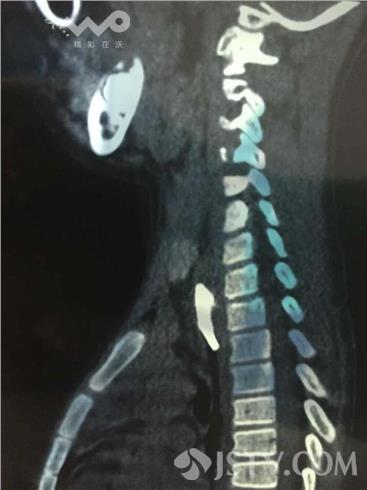

在儿童医院办公室,荔枝新闻通讯员见到了这块儿被取出来的u型猪骨,至少2cm长,两端十分尖锐。该院消化内科内镜室副主任医师练敏向笔者介绍,CT片显示u型猪骨头很大,两个尖端牢牢卡在食管上端的软组织里面,骨头非常粗,非常硬。“虽然以往取出的异物不计其数,但这么大的异物、卡得这么死的还是头一次。而且这块猪骨靠近主动脉和心脏,距离主动脉血管仅2公分,食管壁已有两个可疑创孔,如果刺破附近的心脏,后果不堪设想。”练敏这样说道。